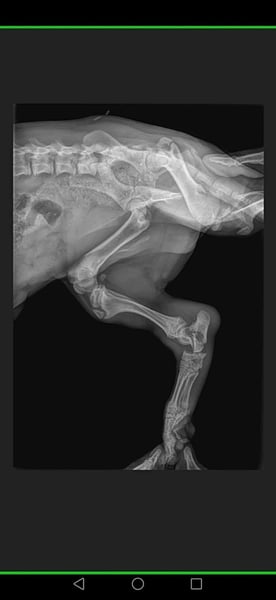

▪️ ausgesetzt auf der Straße mit einem gebrochenen Bein und einer riesengroßen Hernie...

Mit einer Hernie... Eine Luxation und ein Bruch am Bein

wurde er von einer Tierschützerin auf der Straße aufgegriffen..

Und der süße kleine Mann wurde operiert..

▪️Hernie operiert und Kastration durchgeführt...

▪️ Als die erste OP verheilt war, wurde PomPom nach vorheriger Absprache noch noch einige weitere Male unserem Tierarzt vorgestellt..

▪️Um zu schauen ob man an seinem Beinchen noch operieren muss.....

Oder ob man es so lässt...

weil man auch manchmal durch eine OP nichts verbessern,

sondern eher schlimmer machen kann.

⏯️Weil oft auch weniger mehr ist⏮️

Es wurde dann festgestellt der Bruch wächst sehr gut zusammen und der kleine Mann, wird vermutlich keine Einschränkungen mehr haben.

▪️ Wir haben damals gemeinsam mit unserem Tierarzt vereinbart, den kleinen Mann über einen längeren Zeitraum alle paar Monate regelmäßig vorzustellen, ob sich noch irgendetwas nachteilig verändern würde.

▪️ PomPom wurde von unserem Tierarzt, nach der ersten großen OP in regelmäßigen Abständen wieder vorgestellt und der Bruch wurde immer wieder kontrolliert.

▪️ Und die Meinung unseres tollen Tierarztes war wie immer richtig.

▪️Der komplizierte Bruch verheilte perfekt ohne weitere OP problemlos.

▪️ PomPom läuft heute ohne weitere gesundheitliche Einschränkungen.

▪️Er humpelt nicht, er ist ein süßer kleiner Feger der nun endlich nach Hause möchte.